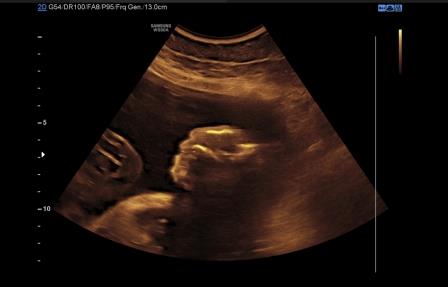

La diagnosi ecografica è relativamente semplice. A 11-12 settimane la volta cranica è assente mentre gli emisferi cerebrali sono ancora riconoscibili e circondati da una sottile membrana a diretto contatto con il liquido amniotico ( acrania-exencefalia ). In sezione coronale l'estremo cefalico assume un aspetto "a mickey mouse"determinato dalla visualizzazione degli emisferi cerebrali come due strutture semicircolari al disopra delle orbite.

Dopo la 12a settimana per il diretto contatto col liquido amniotico ed i traumi determinati dal contatto con la parete uterina l'encefalo si trasforma in una massa di tessuto molle aderente alla base del cranio determinandosi il quadro dell'anencefalia caratterizzato dall'assenza della volta cranica e da tessuto cerebrale scarsamente rappresentato.

In sezione coronale, per la presenza di macroftalmia, l'estremo cefalico assume il tipico aspetto "a rana".